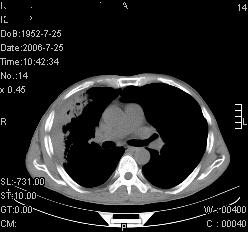

患者,男,54岁,咳嗦,咳痰20天。抗炎治疗2周。现esr76mm/h,目前患者症状明显好转,但发现两次ct片未见明显变化。两次分别做与7.25、7.31。第一次诊断右肺上叶炎症累计胸膜。大家看,从影像上内排除结核吗?

结核的可能性非常大,右上肺病变应该考虑干酪性肺炎。理由:

1.纵隔内多发淋巴结肿大。

2.esr76mm/h。

3.虽经抗炎治疗肺窗病灶有所吸收、减小,但纵隔窗病灶形态、密度、范围无明显变化。如果是单纯的大叶性肺炎,“抗炎治疗2周,目前患者症状明显好转”病灶应该基本消散了,至少也处于吸收消散期,密度变淡、范围变小。同时本病例所示其内的密度不均匀,见多发大小不一空洞样影也不符合大叶性肺炎吸收消散期表现。

病灶特点:片状 索条 结节混杂影,部分融合,密度不均,广泛累及相应胸膜.

临床治疗;二周未吸收.但症状好转.

多考虑:肺结核.